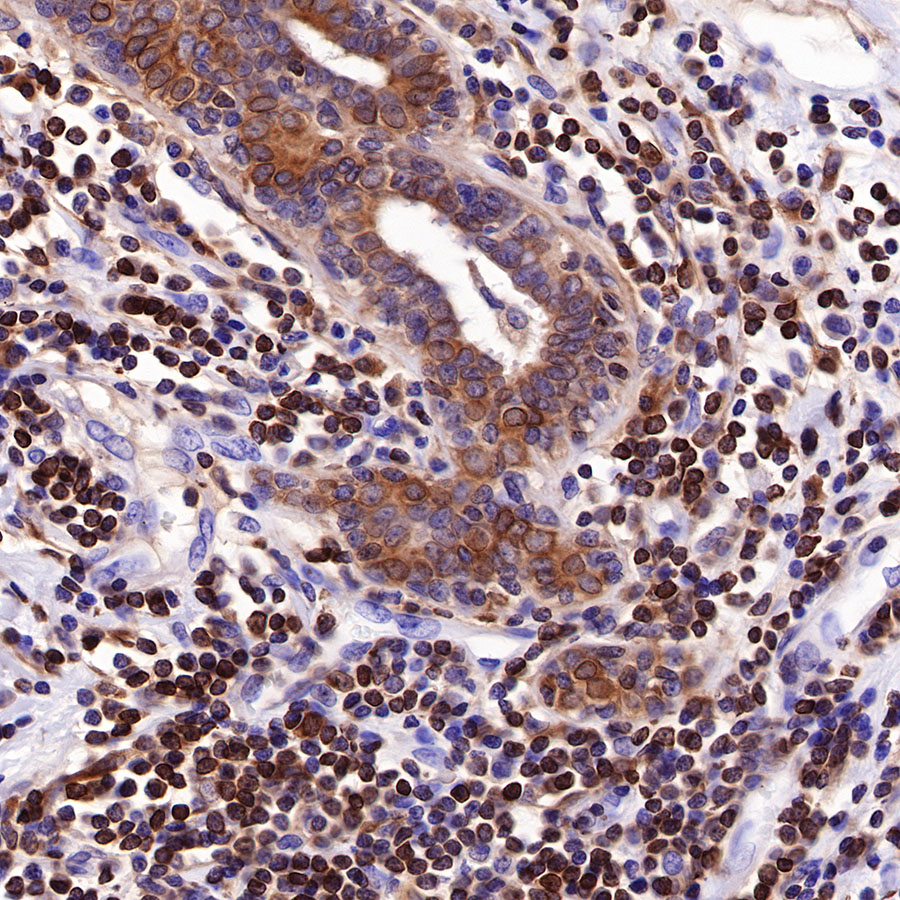

Picture

Picture

Immunohistochemistry